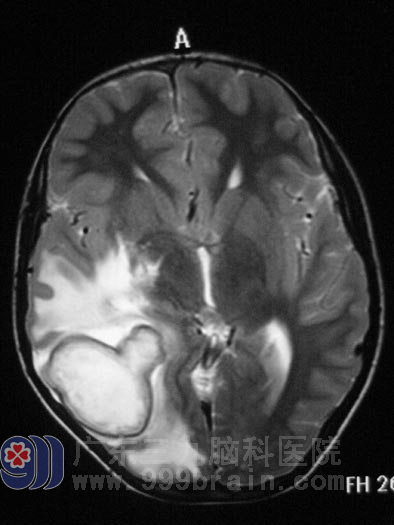

俗话说:屋漏偏逢连夜雨,船迟又遇打头风。几个月前小马无明显诱因开始头痛,呈胀痛感,当时无发热,到当地医院以感冒对症处理后症状稍缓解,但之后反复头痛发作,间断呕吐。1月前小马突发高热,体温达39度,入当地医院行头颅MR示“双侧大脑半球多发占位,脑水肿明显,考虑多发脑脓肿可能”,医生建议手术治疗,但考虑到小马情况特殊,加上当地医院医疗设备、技术都不能保证,所以不敢冒然手术。“十多年来我们都没有放弃,难道现在就这样放弃了?”小马的父亲越想越不甘心,遂开始四处打听,经一朋友介绍得知了广东三九脑科医院,父子一行人挎上包裹,踏上求医的路程。

脑脓肿

广东三九脑科医院神经外五科鲁明主任检查小马后,发现他颅内压比正常人稍高,心脏彩超示“先天性心脏病,室间隔缺损”, 二尖瓣听诊区可闻收缩期杂音,鲁主任同全院资深专家会诊后一致认为小马可以耐受手术。2011年2月22日小马被送入手术室行“右侧顶枕叶脑脓肿穿刺引流术”,术中严密监测心电变化,尽量减少手术时间,术中见黄绿色脓液涌出,反复冲洗脓腔,术中出血少,术程顺利。术后并没有放松警惕,继续予罗氏芬冲洗脓腔,继续抗感染、营养心肌、止血对症支持治疗。当我们见到小马时,他已康复了,小马的父亲拉着医生的手激动地直说谢谢。